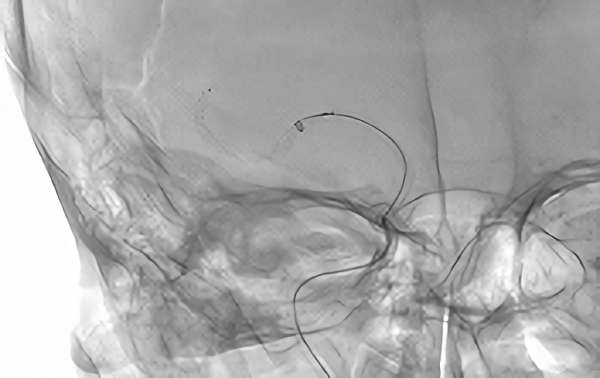

829

'20年6月21日

血栓性脳梗塞

80代

手術中1

手術中2